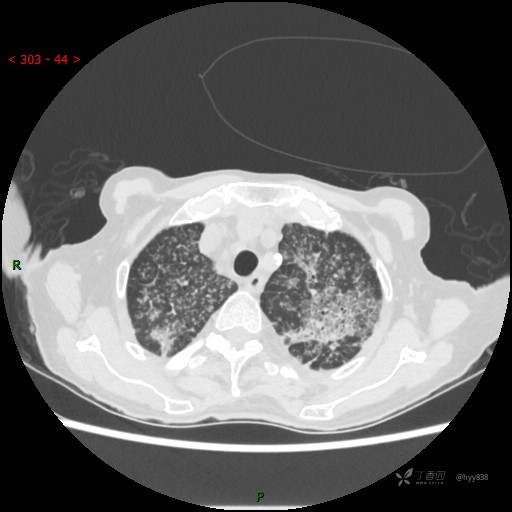

肺部弥漫性、疑难病变,感染或肿瘤?一元论或二元论?贴贴精彩---结果公布~

患者性别:女

患者年龄:73岁

主诉:反复发热10余天

简要病史:患者10余天劳累后出现发热,最高体温达39.5℃,无畏寒、寒战、鼻塞、流涕,无头晕、头痛,无心慌、胸闷、胸痛,无咳嗽、咳痰、气喘,无反酸、烧心、恶心呕吐,无腹痛、腹胀等不适,于2022-5-31至当地中医医院住院治疗,诊断为重症肺炎,予以抗感染、抗病毒等对症支持治疗,仍反复发热,现为求进一步诊治,至我院门诊就诊,门诊以“重症肺炎”收入我科。 起病以来,患者精神、饮食、睡眠差,大小便正常,体力下降,体重无明显变化。

体格检查:T 38℃ P 102次/分 R 17次/分 BP 142/85mmHg,SPO2 84%(未吸氧)。神志清楚,呼吸稍急促,查体合作,咽部充血,未见明显脓点,颈软,全身皮肤黏膜及巩膜未见黄染,浅表淋巴结未触及肿大。双肺呼吸音粗,未闻及明显干湿啰音,HR 102次/分,律齐,各瓣膜区未闻及病理性杂音。腹部平坦,腹软,无压痛,肝脾肋下未触及肿大。双下肢轻度水肿。生理反射存在,病理征阴性。

临床诊断:重症肺炎

胸部CT平扫